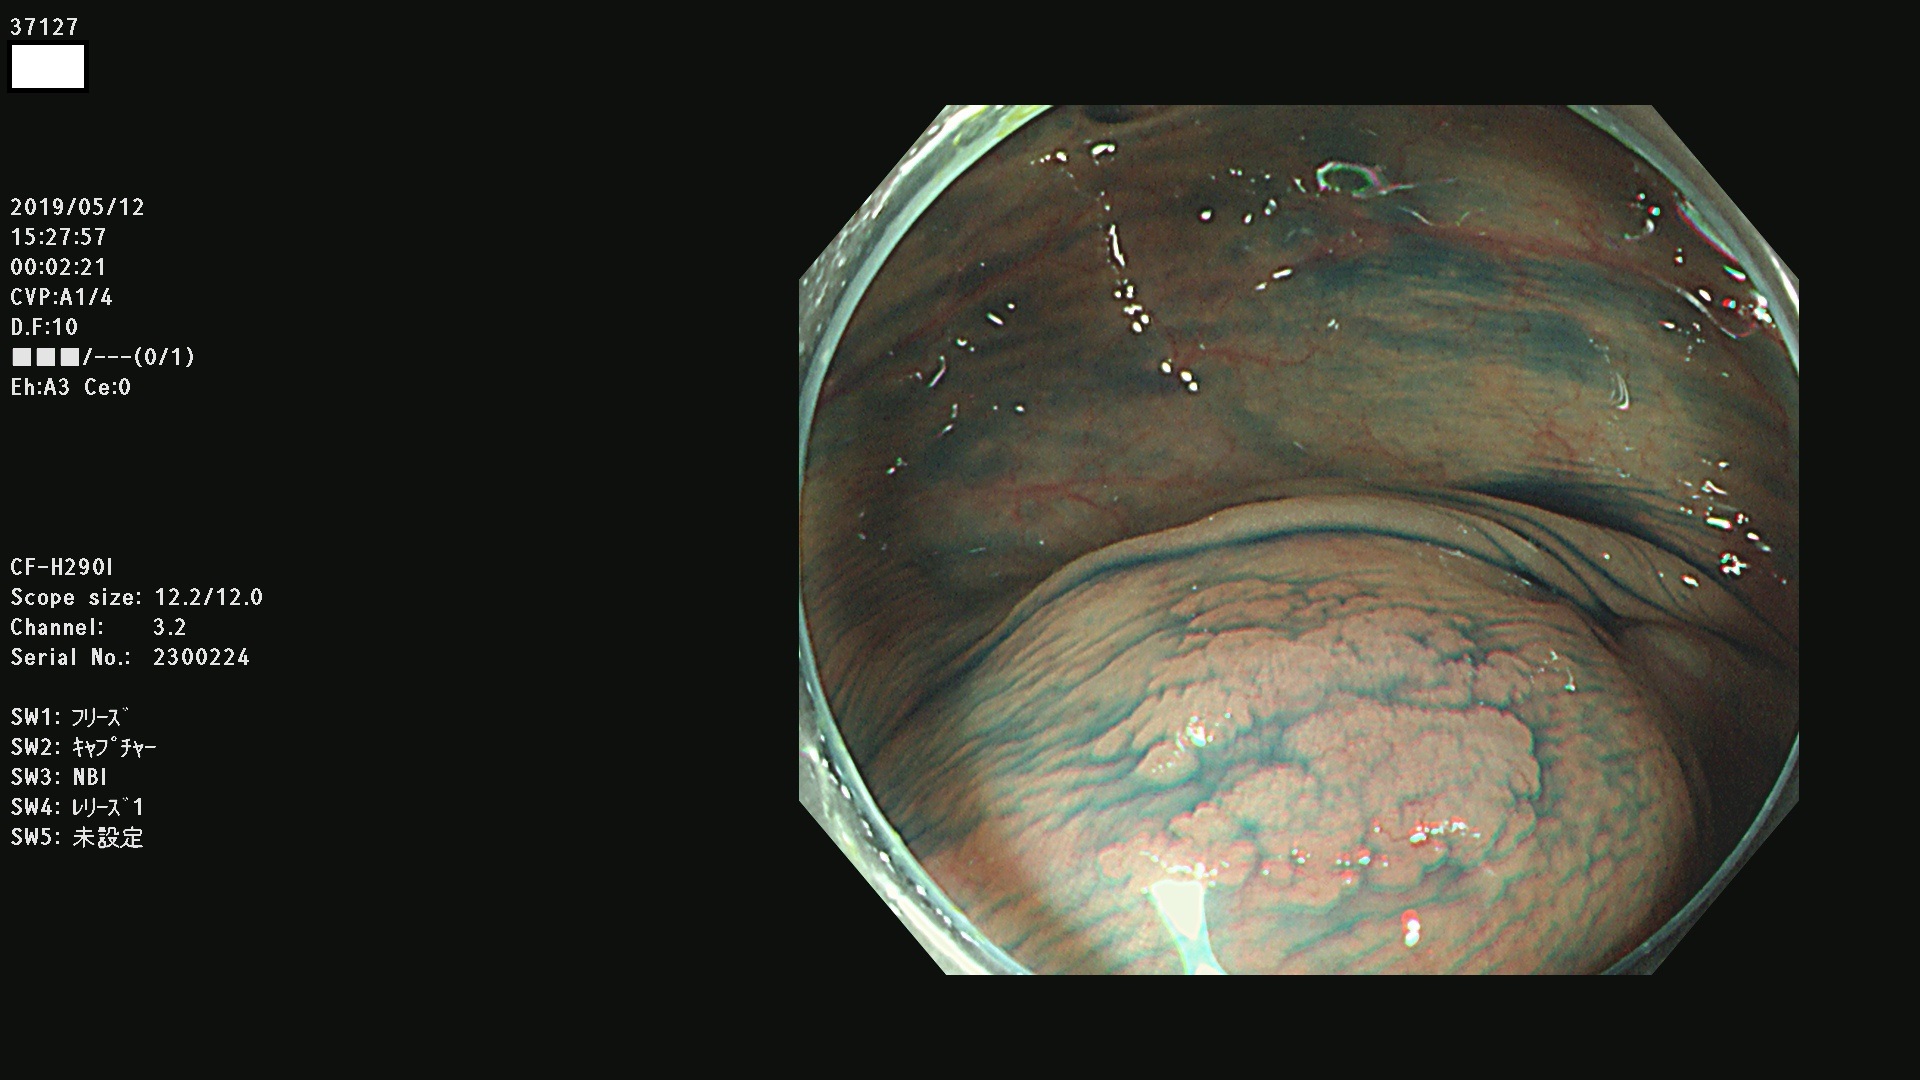

37100 37101 37102 37104 37106 37108 37110 37111 37112 37113 37115 37118(SSAPのみ) 37120 37122 37123 37124 37127(SSAPのみ) 37128(SSAPのみ) 37131 37132 37133 37134 37135 37139 37141 37142 37143 37144(SSAPのみ) 37145 37147(SSAPのみ) 37148 37149 37150 37153 37154 37157 37159 37161 37162 37163 37164 37165 37166 37167 37168 37169 37170 37171 37172 37173 37175(SSAPのみ) 37176 37177 37178 37180(SSAPのみ) 37181 37184 37185 37186 37187 37188 37189 37190 37192 37194 37197 37198

発見困難で危険性の高い平坦型病変(上記100名より抽出)